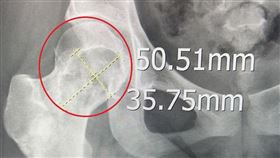

正值18歲的許小姐因右邊髖關節不定時產生疼痛感,起初...

2023/03/27 08:49